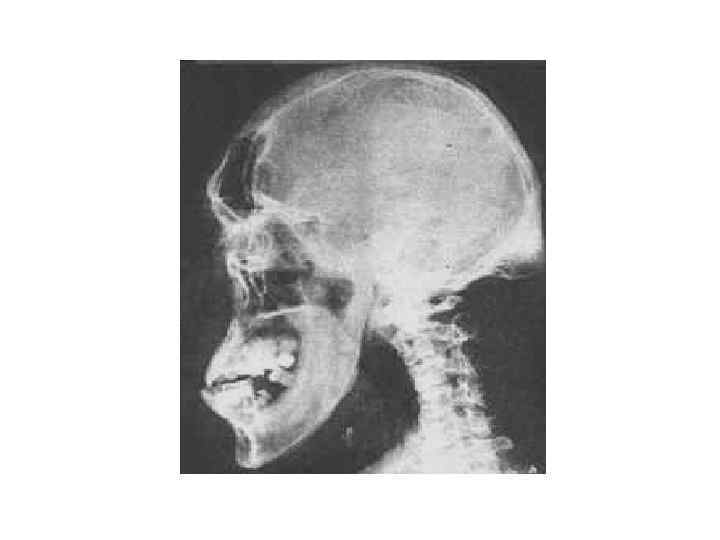

Акромегалия

Акромегалия

Субъективные признаки акромегалии • • • • Увеличение кистей и стоп — 100%; Изменение внешности — 100%; Избыточная потливость — 83%; Головная боль — 80%; Парестезии — 71%; Боли в суставах и спине — 69%; Потливость — 62%; Нарушения менструального цикла — 58%; Общая слабость и снижение трудоспособности — 54%; Увеличение веса — 48%; Снижение либидо и потенции — 42%; Нарушение зрения — 36%; Сонливость днем — 34%; Гипертрихоз — 29%; Сердцебиение и одышка — 25%.

Субъективные признаки акромегалии • • • • Увеличение кистей и стоп — 100%; Изменение внешности — 100%; Избыточная потливость — 83%; Головная боль — 80%; Парестезии — 71%; Боли в суставах и спине — 69%; Потливость — 62%; Нарушения менструального цикла — 58%; Общая слабость и снижение трудоспособности — 54%; Увеличение веса — 48%; Снижение либидо и потенции — 42%; Нарушение зрения — 36%; Сонливость днем — 34%; Гипертрихоз — 29%; Сердцебиение и одышка — 25%.

Объективные признаки акромегалии • • • • • Увеличенные кисти и стопы — 100%; Укрупнение черт лица — 100%; Диастема — 72%; Прогнатизм — 19%; Отечность мягких тканей — 100%; Наличие аденомы гипофиза — 100%; Увеличение щитовидной железы — 65%; зоб — 41%; снижение уровня тироксина в крови — 14%; Проксимальная миопатия — 55%; Туннельный синдром карпального канала — 41%; Гиперпролактинемия — 40%; галакторея — 8%; Сужение полей зрения — 40%; Повышенная влажность и "жирность" кожи — 39%; Сниженная гонадотропная секреция — 37%; Повышение АД — 31%; Нарушенная толерантность к глюкозе — 30%; клинический диабет — 29%; Снижение функции коры надпочечников — 24%; Деформация скелета и суставов — 21%; Почечнокаменная болезнь — 12%; ИБС – 9%.

Объективные признаки акромегалии • • • • • Увеличенные кисти и стопы — 100%; Укрупнение черт лица — 100%; Диастема — 72%; Прогнатизм — 19%; Отечность мягких тканей — 100%; Наличие аденомы гипофиза — 100%; Увеличение щитовидной железы — 65%; зоб — 41%; снижение уровня тироксина в крови — 14%; Проксимальная миопатия — 55%; Туннельный синдром карпального канала — 41%; Гиперпролактинемия — 40%; галакторея — 8%; Сужение полей зрения — 40%; Повышенная влажность и "жирность" кожи — 39%; Сниженная гонадотропная секреция — 37%; Повышение АД — 31%; Нарушенная толерантность к глюкозе — 30%; клинический диабет — 29%; Снижение функции коры надпочечников — 24%; Деформация скелета и суставов — 21%; Почечнокаменная болезнь — 12%; ИБС – 9%.